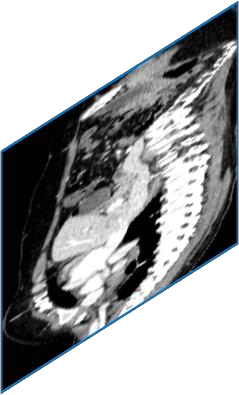

Due to the constraints of the imaging device and high cost in operation time, computer tomography (CT) scans are usually acquired with low intra-slice resolution. Improving the intra-slice resolution is beneficial to the disease diagnosis for both human experts and computer-aided systems. To this end, this paper builds a novel medical slice synthesis to increase the between-slice resolution. Considering that the ground-truth intermediate medical slices are always absent in clinical practice, we introduce the incremental cross-view mutual distillation strategy to accomplish this task in the self-supervised learning manner. Specifically, we model this problem from three different views: slice-wise interpolation from axial view and pixel-wise interpolation from coronal and sagittal views. Under this circumstance, the models learned from different views can distill valuable knowledge to guide the learning processes of each other. We can repeat this process to make the models synthesize intermediate slice data with increasing inter-slice resolution. To demonstrate the effectiveness of the proposed approach, we conduct comprehensive experiments on a large-scale CT dataset. Quantitative and qualitative comparison results show that our method outperforms state-of-the-art algorithms by clear margins.